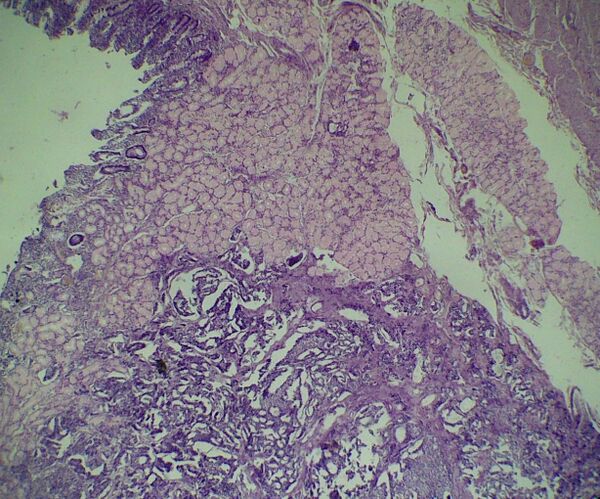

Карциноид

Карцино́ид — опухоли, исходящие из энтерохромаффинных ЕС-клеток, локализующихся в ЖКТ от кардиального отдела желудка до прямой кишки, поджелудочной железе, желчном пузыре, урогенитальном тракте, слизистой оболочке бронхов и вилочковой железе.

Характеризуется приступами покраснения лица и верхней половины туловища, сопровождается гипертонией. Большинство карциноидных опухолей локализуется в тонкой кишке — 30 % из них множественные, растут медленно, как правило, не более 1 см в диаметре, редко 2 см в диаметре, с гладкой поверхностью, содержащей желтоватые или коричневатые узлы, располагаются в подслизистом слое, часто злокачественные[3]. Встречаются в возрасте 50…60 лет.

Опухоли секретируют главным образом серотонин, а также калликреин, гистамин, простагландины, нейропептид К, нейрокинин А, вещество Р, которые обладают вазоактивными свойствами. До возникновения клинических симптомов опухоль может существовать 5…10 лет бессимптомно[3].